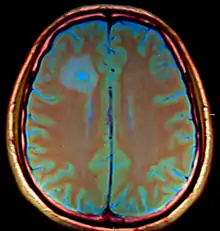

| Brain abscess in a person with a CSF shunt. The abscess is the darker gray region in the lower left of the image (corresponding to the right parietal lobe). The lateral ventricles are visible in black in the center of the brain, adjacent to the abscess.[1] | |